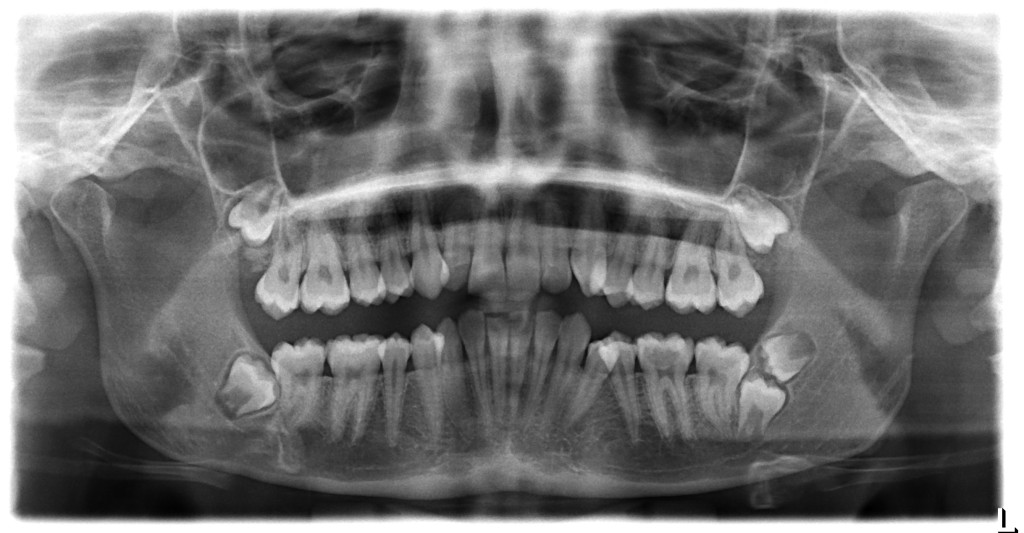

• a contenuto generico (carie, estrazioni dentali, granulomi, ascessi, dolore denti, protesi, impianti, ecc.. ), se non dettagliate nei particolari e, possibilmente, corredate da documentazione ( RX endorali, Ortopanoramiche, immagini fotografiche, ecc... );

• a contenuto specifico ( malocclusioni, disfunzioni ATM, denti storti, ecc...) se prive di documentazione allegata (RX arcate dentarie, Teleradiografia latero-laterale e postero-anteriore, Stratigrafia a bocca aperta e bocca chiusa, TAC (Cone Beam) ai condili, immagini fotografiche, ecc... );